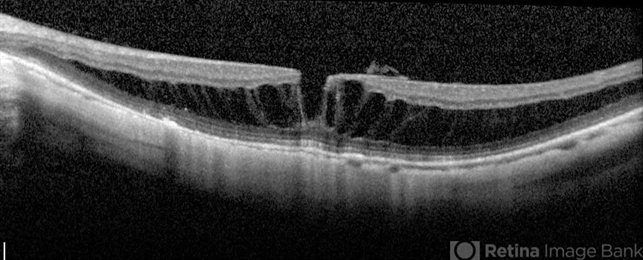

- myopic macular schisis, lamellar macular hole

- Spectral domain OCT of patient with high myopia and myopic macular schisis resulting in lamellar macular hole.